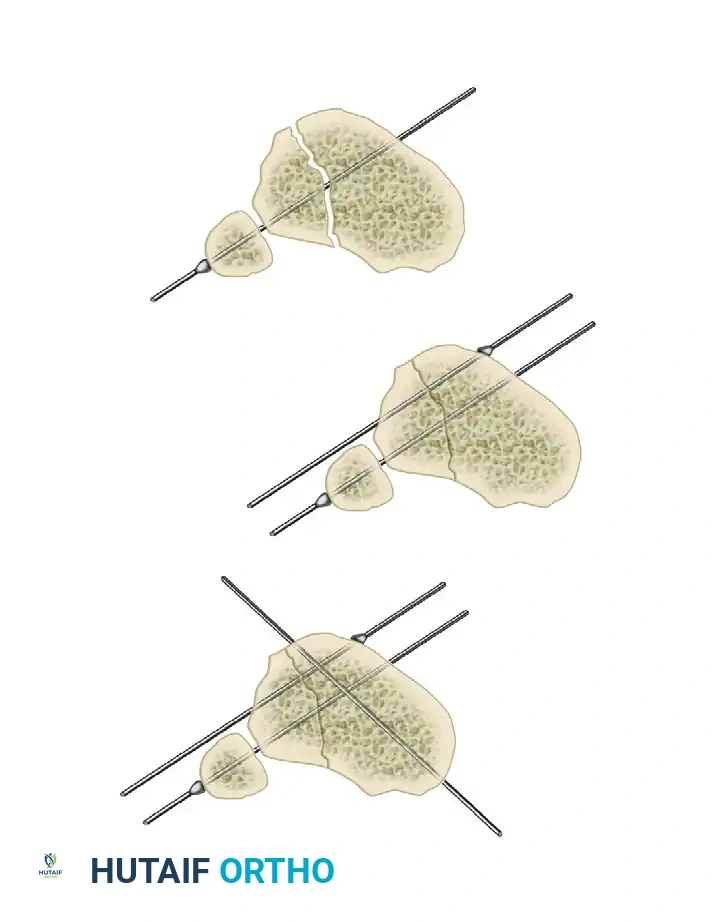

Step 2: Reference Wire Placement and Frame Suspension

To establish the foundational alignment of the construct, proximal and distal reference wires must be placed accurately.

- Hold the frame in the desired position and insert proximal and distal transverse reference wires. These wires must be placed parallel to the knee joint line (proximal) and the ankle joint line (distal).

- As these reference wires are secured to the frame and tension is applied, initial correction of the fracture in the coronal plane is achieved.

Alternative Suspension Technique:

If manual holding is difficult, suspend the frame using ordinary surgical suction tubing. Place the tubing around the extremity and secure it to the frame with towel clips.

- Eccentrically tilt the proximal and distal rings until they are perfectly parallel to the knee and ankle joints, respectively.

- After securing fixation with at least two tensioned wires to both the proximal and distal rings, adjust the threaded rods to bring these two rings parallel to their counterparts in the center of the frame. This maneuver facilitates further indirect fracture reduction.

Step 3: Multi-Planar Fracture Reduction Using Olive Wires

- Coronal Plane Correction: Use arched olive wires for final fracture reduction. For residual displacement in the coronal plane, place an olive wire in a transverse fashion (ensuring it passes through a safe anatomical zone).

- Apply tension to the wire without securing it tightly to the frame on the opposite side. The tensioner will pull the olive—and consequently the bone fragment—toward the tensioner, correcting the translation.

- Use continuous image intensification to ensure adequate reduction is achieved without over-translating the fragment.

- Once adequate correction is obtained in the coronal plane, secure the wire to the frame on the olive side.

- Sagittal Plane Correction: If further correction is required in the sagittal plane, connect another olive wire in an arched fashion. Tensioning this arched wire will impart a directional force vector to the bone, achieving final sagittal alignment.